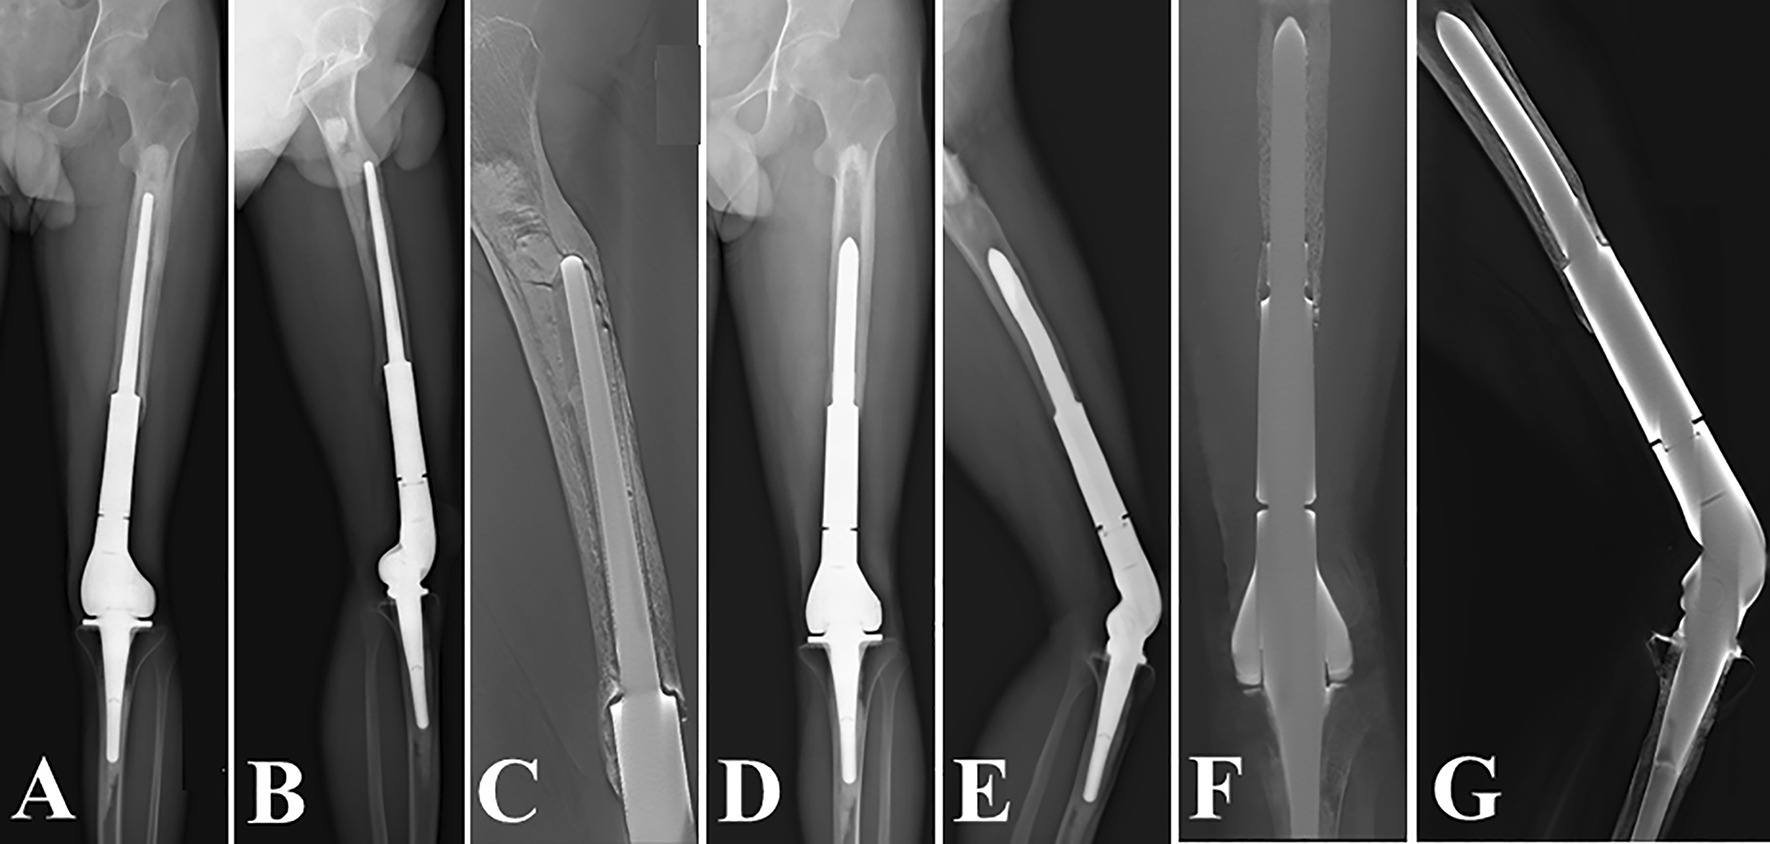

Revision of a Grade I bone loss case with “Short uncemented stem”. A–C preoperative radiographs; the anteroposterior and lateral radiographs (D, E), and the digital tomosynthesis images (F, G) 1 year after revision surgery

Fig. 4.

Revision of a Grade II bone loss case with “Long uncemented stem”. A–C preoperative radiographs; the anteroposterior and lateral radiographs (D, E), and the digital tomosynthesis images (F, G) 3 years after revision surgery